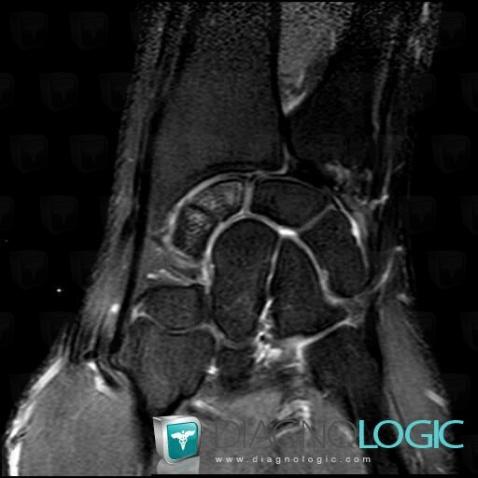

Fracture, Scaphoid, MRI

Here is the specific information in the key image above:

- Diagnosis Fracture, Location(s) Scaphoid, with gamuts Bone marrow edema